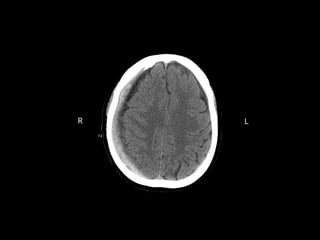

 Mme EW, 80 ans, sexe féminin avec

 Aphasie d’expression/apraxie

 Leger affaissement de l’hémiface droit

Leger affaissement de l’hémiface droit

 Fibrillation Atriale

 Un scanner cérébral non injecté est

Votre analyse

 Quels sont vos trouvailles?

 Quel est votre impression?

 Quel serai votre prémier diagnostic?

Cas #1 - Réponse

 Mme. EW a eu un

Infarctus du Lobe Parietal

Gauche

 La localisation est

compatible avec un

infarctus

ACM

 La cause est une embole

due à la fibrillation atriale